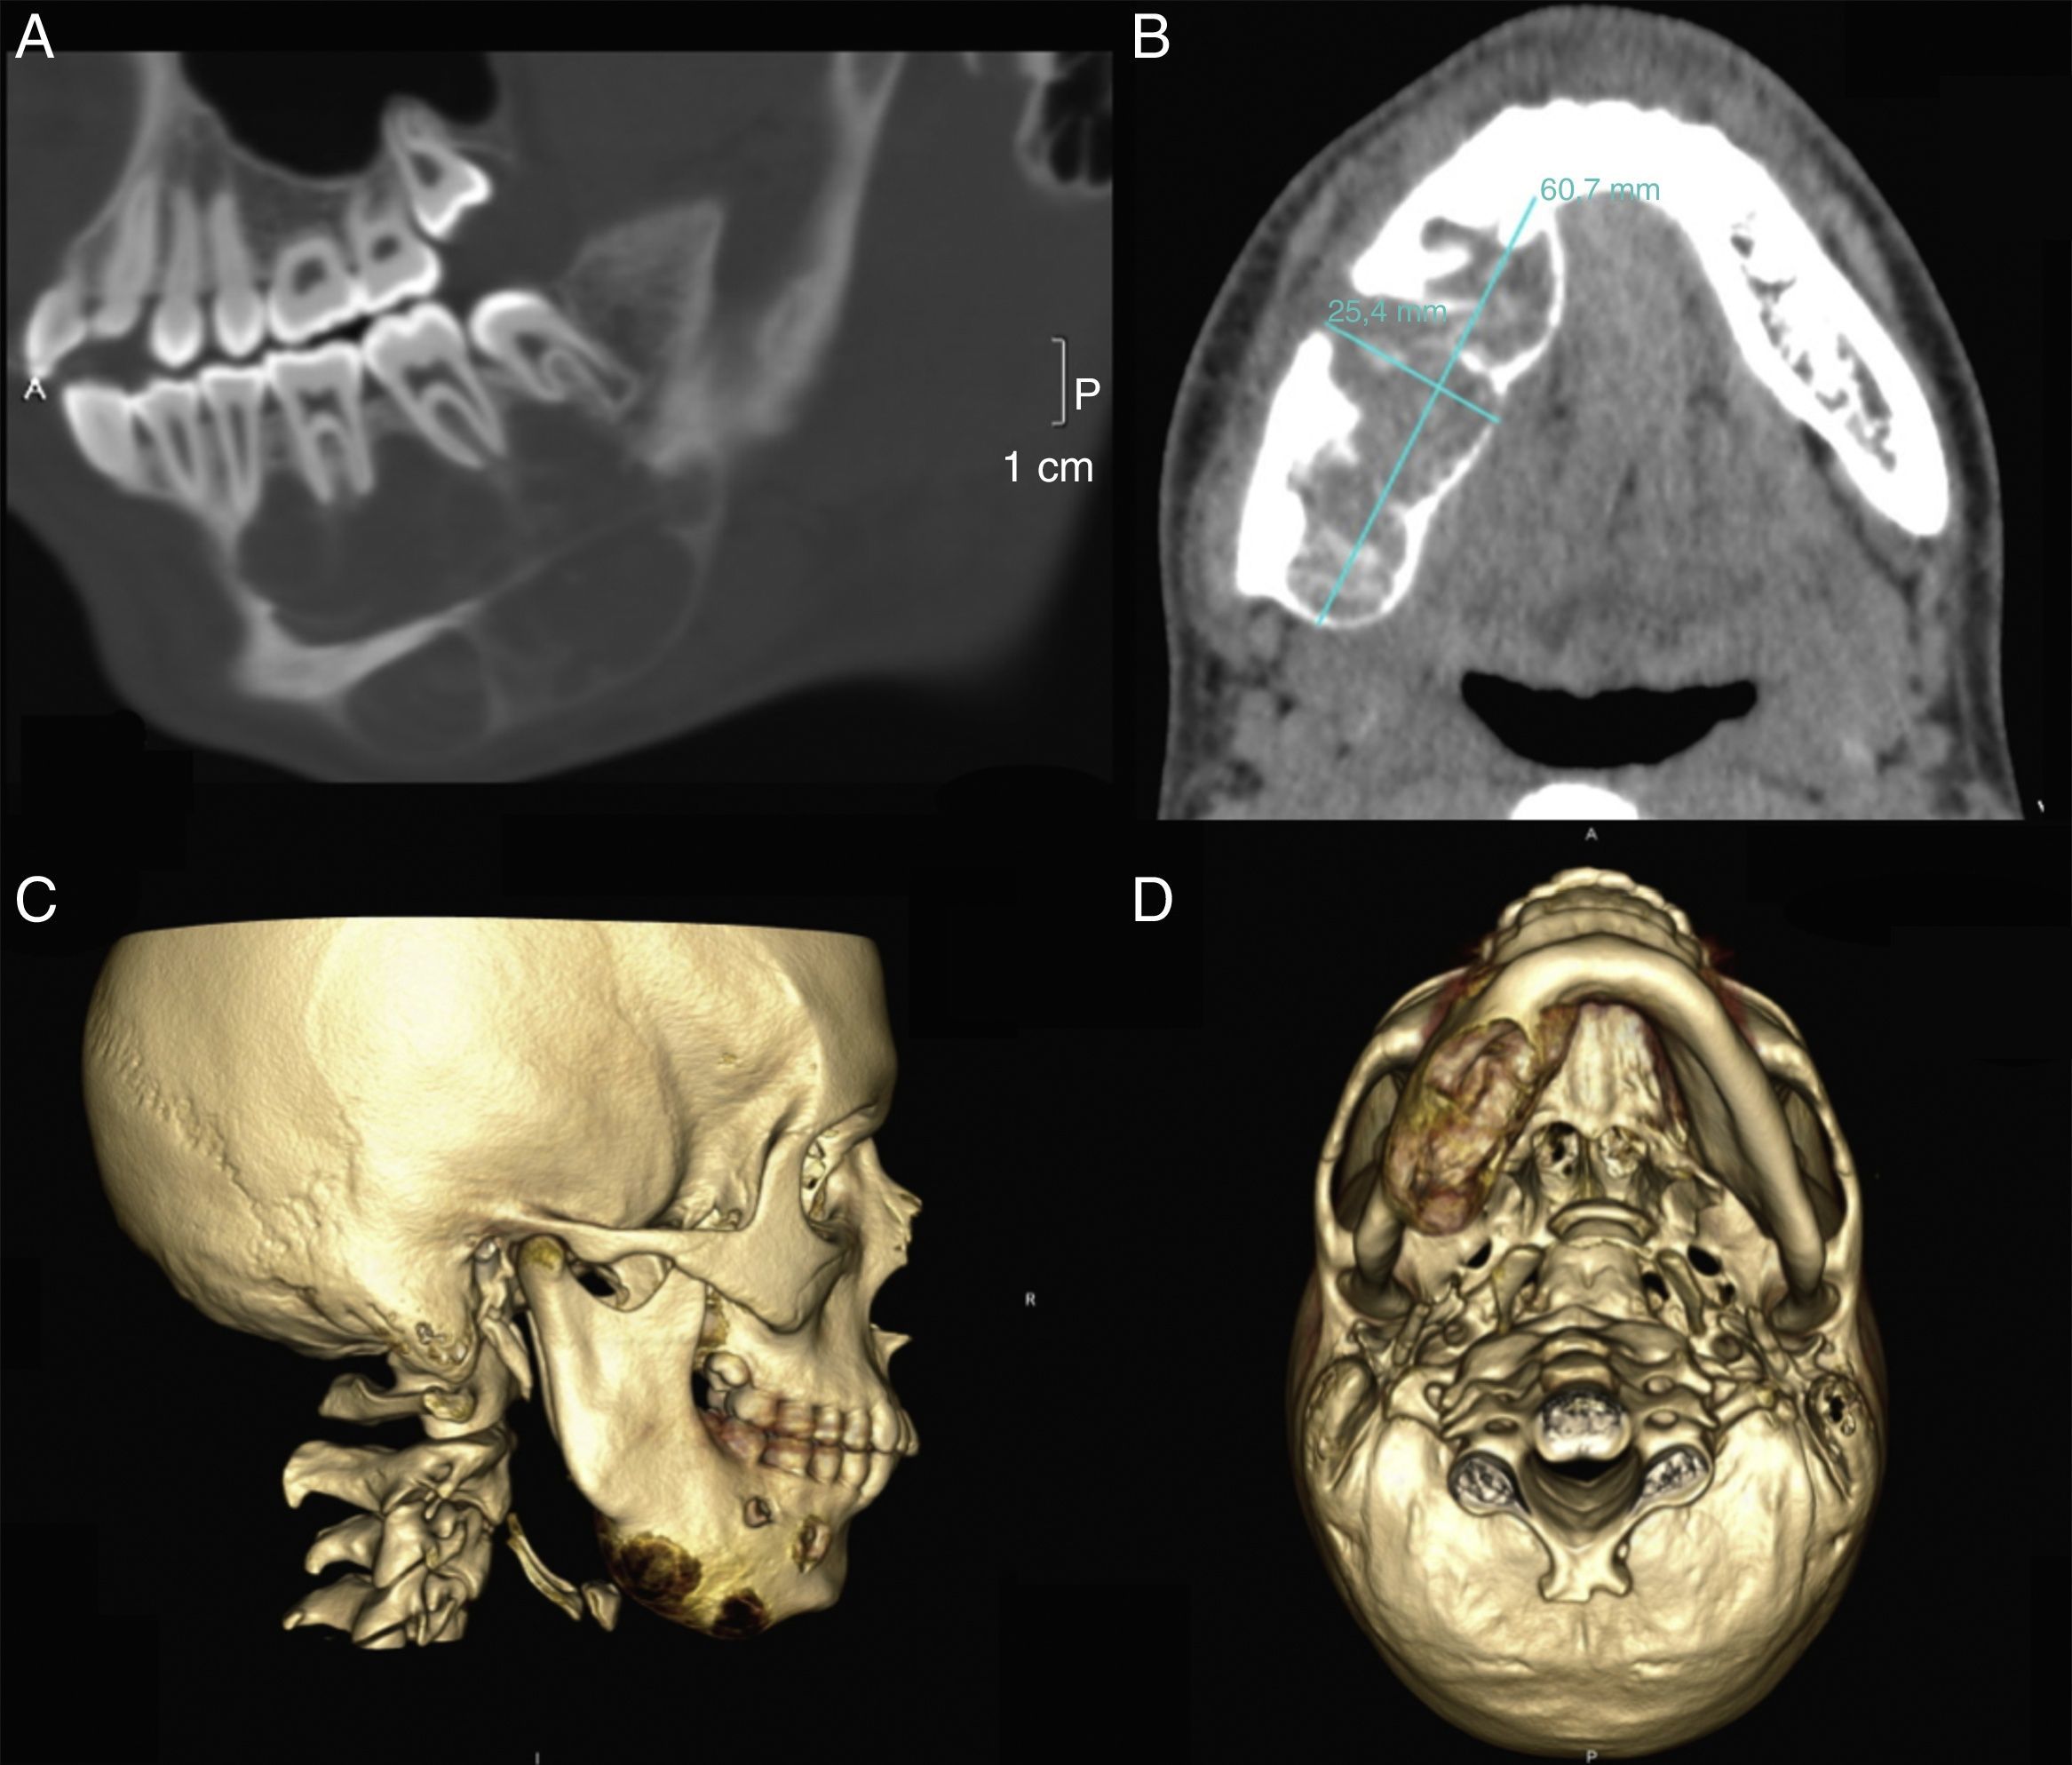

La ortopantomografía confirmó la presencia de una lesión de radiolucidez mixta en cuerpo mandibular derecho con límites poco diferenciados. En el TAC la lesión resultaba ser multilobulada sin signos de rizolisis, y con un discreto desplazamiento inferior del canal del nervio dentario (fig. 1).